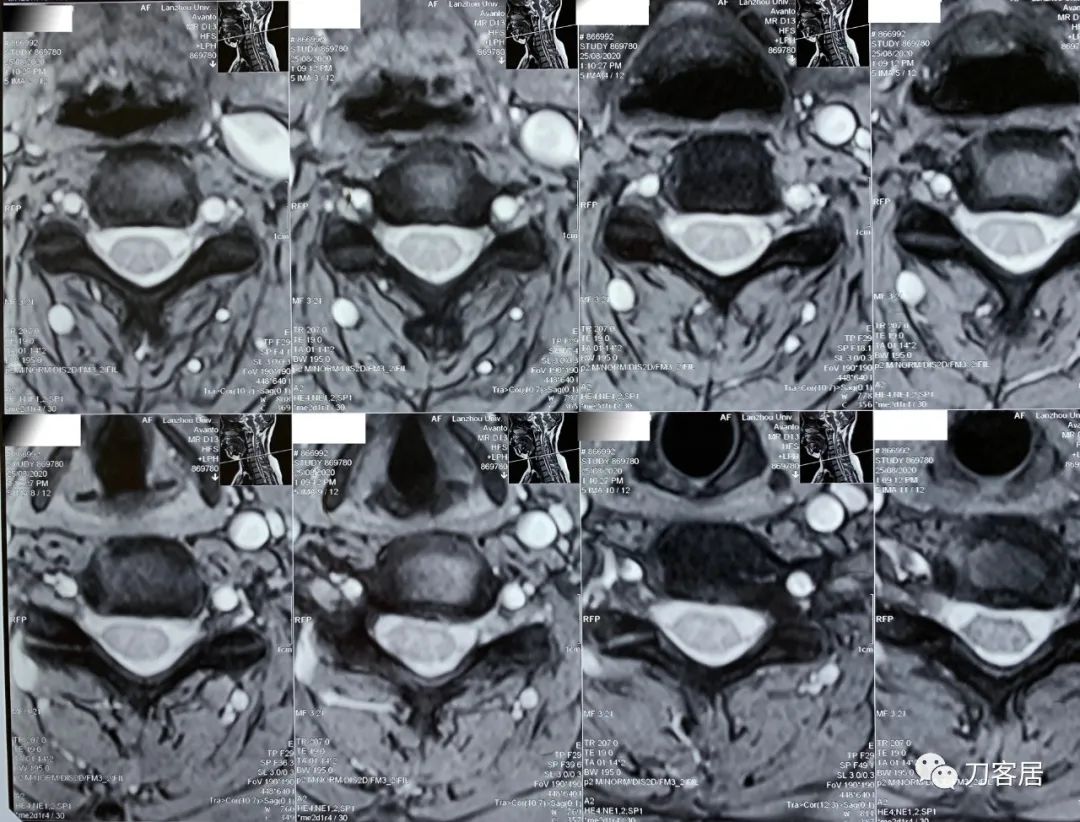

2021年5月17日,西京医院骨科门诊找我就诊,自带影像学检查资料提示腰椎侧弯,腰3-4,腰4-5椎间盘突出,黄韧带肥厚,椎管狭窄。

建议其查双光子骨密度,骨盆正位片以及腰椎间盘平扫。腰椎正侧位X线片以及动力位片,站立位脊柱全长正侧位X线片,以了解其是否有骨质疏松,并了解脊柱侧弯情况,腰椎局部X线表现情况和腰椎间盘突出和椎管狭窄情况。

从这个患者的影像资料分析,颈椎间盘突出问题不大,没有明确的上位神经元损伤表现,所以,不考虑颈椎和胸椎问题。腰椎侧弯畸形,但不严重。因为存在腰椎侧弯,使得腰椎MRI在扫描切面的时候,显示的椎间盘突出或椎管狭窄会有一定的误差,所以,又加做了经椎间盘的CT平扫,影像表现并不严重,综上,腰椎间盘突出,腰椎管狭窄,腰椎侧弯,不考虑手术治疗。同时,患者的主要痛苦是心理疾病,而不是器质性疾病,所以,以心身疾病治疗为主。虽然患者骨密度检查结果提示正常,但X线片显示骨质疏松,且其症状也与骨质疏松的症状有符合之处,比如静息痛,不能入睡,动作及姿势变换时痛加重等,所以,给予实验性抗骨质疏松治疗,以观疗效。